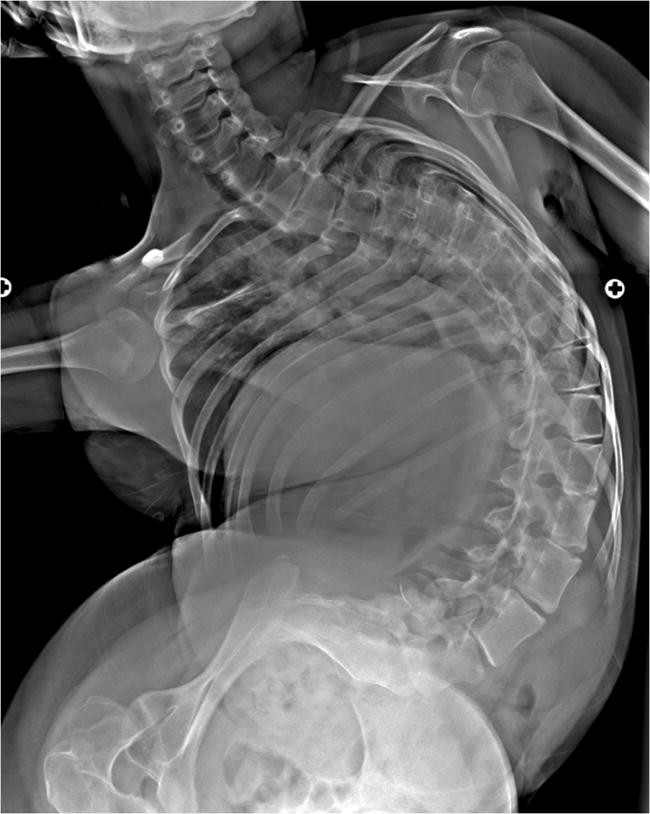

يُعدّ اعوجاج العمود الفقري (Scoliosis) من المشكلات الشائعة التي تصيب الأطفال المصابين بـ الشلل الدماغي (Cerebral Palsy – CP)، وهي حالة عصبية تؤثر على حركة العضلات وتوازن الجسم. ومع أن هذا الاعوجاج يبدأ عادة في الطفولة أو المراهقة، إلا أن الدراسات الحديثة تؤكد أن الاعوجاج قد يستمر في التفاقم حتى بعد اكتمال النمو العظمي، أي بعد سن البلوغ، وهو ما قد يثير قلق الأهل والأطباء حول مدى خطورة هذه المشكلة وكيفية متابعتها.

في هذه المرحلة، يتوقع الأطباء أن يستقر شكل العمود الفقري، لكن عند بعض المرضى المصابين بالشلل الدماغي، قد يستمر الاعوجاج في التفاقم رغم توقف النمو، وهو ما يجعل المراقبة المستمرة أمرًا ضروريًا.

حلّلت المراجعة المنهجية 15 دراسة علمية أُجريت بين عامي 1968 و2024، وبلغ مجموع المشاركين 2569 مريضًا مصابًا بالشلل الدماغي تمت متابعتهم بعد سن الخامسة عشرة.

بحسب التحليل، فإن الزيادة السنوية في زاوية الاعوجاج تتراوح بين 1.4 و3.5 درجات في السنة، وقد تصل في بعض الحالات إلى مستويات أكبر.

إذا كان لدى المريض اعوجاج بمقدار 40 درجة عند اكتمال النمو، فقد يزداد بمقدار 10 إلى 20 درجة إضافية خلال عدة سنوات، خصوصًا في الحالات التي تتوافر فيها عوامل خطر معينة.

المرضى الذين كانت زاوية الاعوجاج لديهم أكثر من 40 درجة عند نهاية المراهقة هم الأكثر عرضة لتفاقم الحالة.